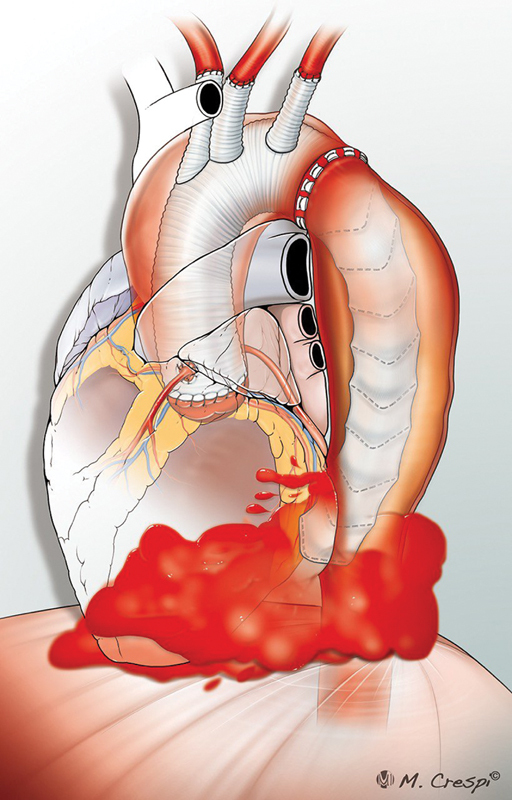

冷冻象鼻(FET)一直是治疗急性和慢性主动脉夹层的主要方法。尽管文献中报道了各种并发症,但据我们所知,血管内移植物导致胸降主动脉破裂的报道尚未发表。我们报告在先前的A型主动脉夹层导致胸降主动脉破裂的保留瓣根置换术后进行FET手术。

The frozen elephant trunk (FET) has been a mainstay in the treatment of acute as well as chronic aortic dissections. Although various complications have been reported in the literature, rupture of the descending thoracic aorta by the endovascular graft has, to our knowledge, not been published. We report an FET procedure following previous valve-sparing root replacement for Type A aortic dissection leading to rupture of the descending thoracic aorta.